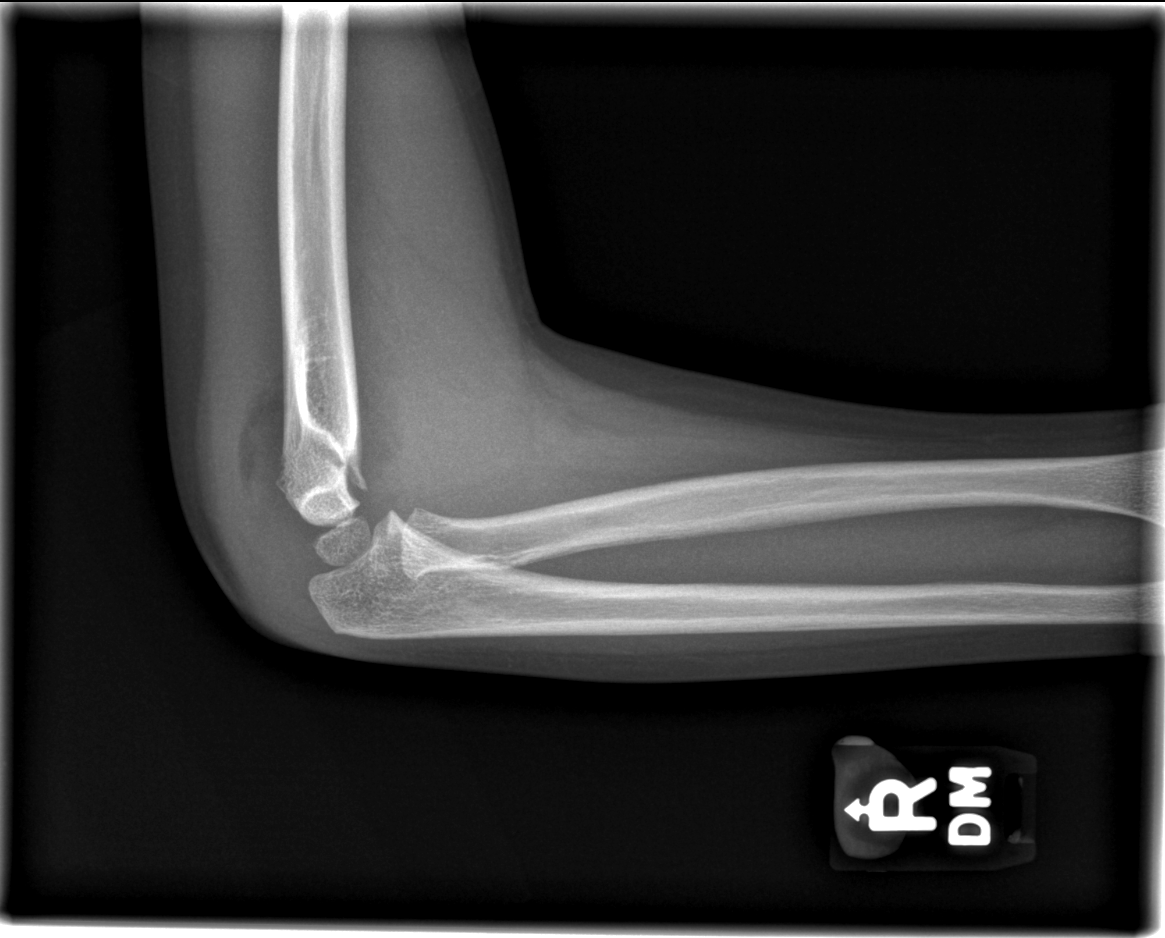

Info Images Findings Impression Reco/Acuity Case Images View Images / Launch Visage Case Notes History 2-month-old presents with decreased right arm movement, increased fussiness, and increased sleepiness for 2 days. Suspected non-accidental trauma. Exam Skeletal survey Prior Study none Dicom View Reference Material

Section 1 Submit Findings CB1550 Findings Skeletal Survey - Technique Check Skull AP/Lat Yes No Cervical and Thoracolumbar spine Yes No Chest X-Ray Yes No Ribs – Left/Right Oblique Yes No Abdominal X-Ray Yes No Pelvis with both hips Yes No Bilateral Humerus, Forearm, Hand Yes No Bilateral Femur, Tibia/fibula, feet Yes No Any additional lateral views of the extremities Yes No The exam is over or under penetrated. Yes No The exam may or may not be limited by overlying structures or soft tissues, body habitus, patient positioning, support devices, or motion. Yes No The area of concern is indicated by the patient, technologist, or care provider. Yes No The area of concern is included on the exam. Yes No Soft Tissues There is soft tissue swelling, indistinctness of fat/muscle planes, gas, or laceration in the area of clinical concern. Yes No There is an effusion, fat pad displacement, or fat fluid level. Yes No There is a radiodense or lucent foreign body. Yes No There are other densities, calcifications, post-surgical changes, or support devices in the soft tissues. Yes No Any support lines/tubes. Yes No Bone There is a break or interruption of the continuity of the cortical or cancellous bone. Yes No There is overriding of the trabeculae with apparent sclerosis. Yes No There is displacement of a fracture fragment. Yes No There is bowing of the bone in addition to the fracture at the apex of the bowed bone concerning for the greenstick. Yes No There is a spiral fracture of the leg concerning for toddler’s fracture. Yes No There is abnormal angulation or bulging of the cortical surface relative to the normal cortex which could be from a buckle or torus fracture. Yes No There is a displaced fragment which may be from avulsion by a tendon, ligament, or joint capsule or from a comminuted or other fracture. Yes No The stress trabeculae or other trabeculae of the cancellous bone are interrupted or otherwise abnormal. Yes No There is subperiosteal or endosteal reaction which could indicate a healing or subacute fracture or other abnormality. Yes No There is hard/soft callus formation. Yes No There is remodeling of the bone. Yes No There is a corner fracture or metaphyseal lesion that could be from nonaccidental trauma. Yes No There are multiple fractures of different ages. Yes No There are vertebral body/spinous process fractures. Yes No There are rib fractures. Location - posterior or lateral. Yes No There is scapular/sternal fracture. Yes No There are fractures of the digits. Yes No There are wormian bones. Yes No There are intrasutural bones. Yes No There is metaphyseal abnormality (lucencies, increased density, erosion) which may be from something other than injury such as stress, metabolic disease (e.g. rickets with loss or distortion of the zone of the provisional calcification), neoplasm (e.g. leukemia), heavy metals, inflammation, or infection. Yes No There are metaphyseal spurs. Yes No There are bony deformities involving multiple bones. Yes No The bones are gracile. Yes No There are non-healing fractures. Yes No There is/are focal or multifocal lytic/lucent, blastic/sclerotic or mixed density lesion(s) or other abnormality. Yes No Overall bone density is increased or decreased with or without thinning or thickening of the cortical or cancellous bone. Yes No Growth plates, ossification centers, apophyses The growth plate(s) is/are abnormal. Yes No There is widening of the physis from a fracture with or without displacement of the epiphysis (Salter-Harris I). Yes No There is a fracture through the physis which then extends into the metaphysis with or without angulation or displacement (S-H II). Yes No There is a fracture through the physis which then extends into the epiphysis and is intra-articular, with or without angulation or displacement (S-H III). Yes No There is a fracture through the metaphysis, physis, and epiphysis which extends into the joint space with or without angulation or displacement (S-H IV). Yes No There is narrowing of the physis from a compression fracture (S-H V). Yes No The apophysis, epicondyle, secondary ossification center, or accessory ossicle is displaced or otherwise abnormal. Yes No The ossification centers are underdeveloped. Yes No Joints and alignment There is an effusion, fat pad displacement, or fat fluid level. Yes No The epiphysis or subchondral bone is fractured, interrupted, flattened, compressed, impacted, displaced, or otherwise abnormal. Yes No There is an intra-articular loose body or chondrocalcinosis. Yes No The joint is widened, narrowed, dislocated, malaligned, or incongruent. Yes No There is pseudoarthrosis. Yes No Other findings There are developmental changes or other anatomic variants or other existing conditions that may or may not be contributing to symptoms which can or should be further evaluated non-emergently or are otherwise incidental. Yes No The remainder of the exam is abnormal for age. Yes No The lungs show focal airspace opacity. Yes No There is pneumothorax. Yes No There is organomegaly. Yes No There is intra-abdominal calcification. Yes No There is displacement of the bowel loops. Yes No There is free intraperitoneal air. Yes No The bowel loops are dilated/obstructed. Yes No There is paraspinal soft tissue abnormality. Yes No